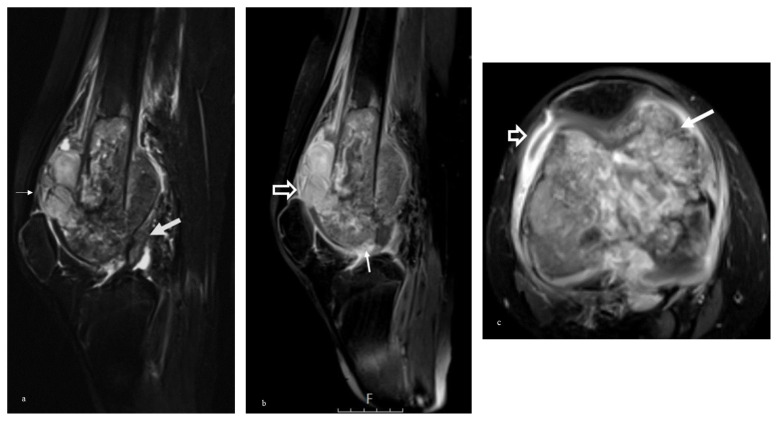

Background/aim: Osteosarcoma is the most common primary malignant bone tumor in adolescents, and the evaluation of joint invasion with MRI is important for treatment planning. This study aimed to investigate the diagnostic value of MRI findings (direct and indirect) for joint invasion in patients diagnosed with osteosarcoma of the knee region.

Materials and methods: The MRI evaluations of 50 knee osteosarcoma patients who underwent surgical resection between 2006 and 2018 were reviewed retrospectively by two radiologists and an orthopedic oncologist. The presence of intrasynovial tumor tissue, intra-articular destruction of cartilage or bone, and invasion of the capsular and cruciate ligament insertions were evaluated as direct findings in the diagnosis of joint invasion on MRI. Indirect findings included tumor size, adjacent epiphyseal bone signal changes- bone marrow infiltration and edema, synovial contrast enhancement, and joint effusion. These findings were scored separately on a 5-point Likert scale and statistically compared with histopathologic results.

Results: The mean age of the patients was 22 years and the gender distribution was 21 females and 29 males. The best predictors for joint invasion were direct visualization of capsular insertion invasion (p < 0.05) and destruction of intraarticular bone (p < 0.05). MRI findings with statistically significant sensitivity and specificity: intrasynovial tumor tissue specificity 76%, sensitivity 58%; intra-articular cartilage destruction specificity 84%, sensitivity 56%; intra-articular bone destruction sensitivity 84%, specificity 48%; capsular insertion invasion sensitivity 92%, specificity 48%. Synovial effusion and contrast enhancement were the most sensitive indirect signs but lacked specificity.

Conclusion: Joint invasion by osteosarcoma can reliably be assessed on preoperative MR images with high sensitivity and specificity. Particularly direct visualization of intrasynovial tumor tissue, capsular insertion invasion, and destruction of intraarticular bone and cartilage, a combination of highly specific direct signs was valuable, while indirect signs were less predictive and specific.